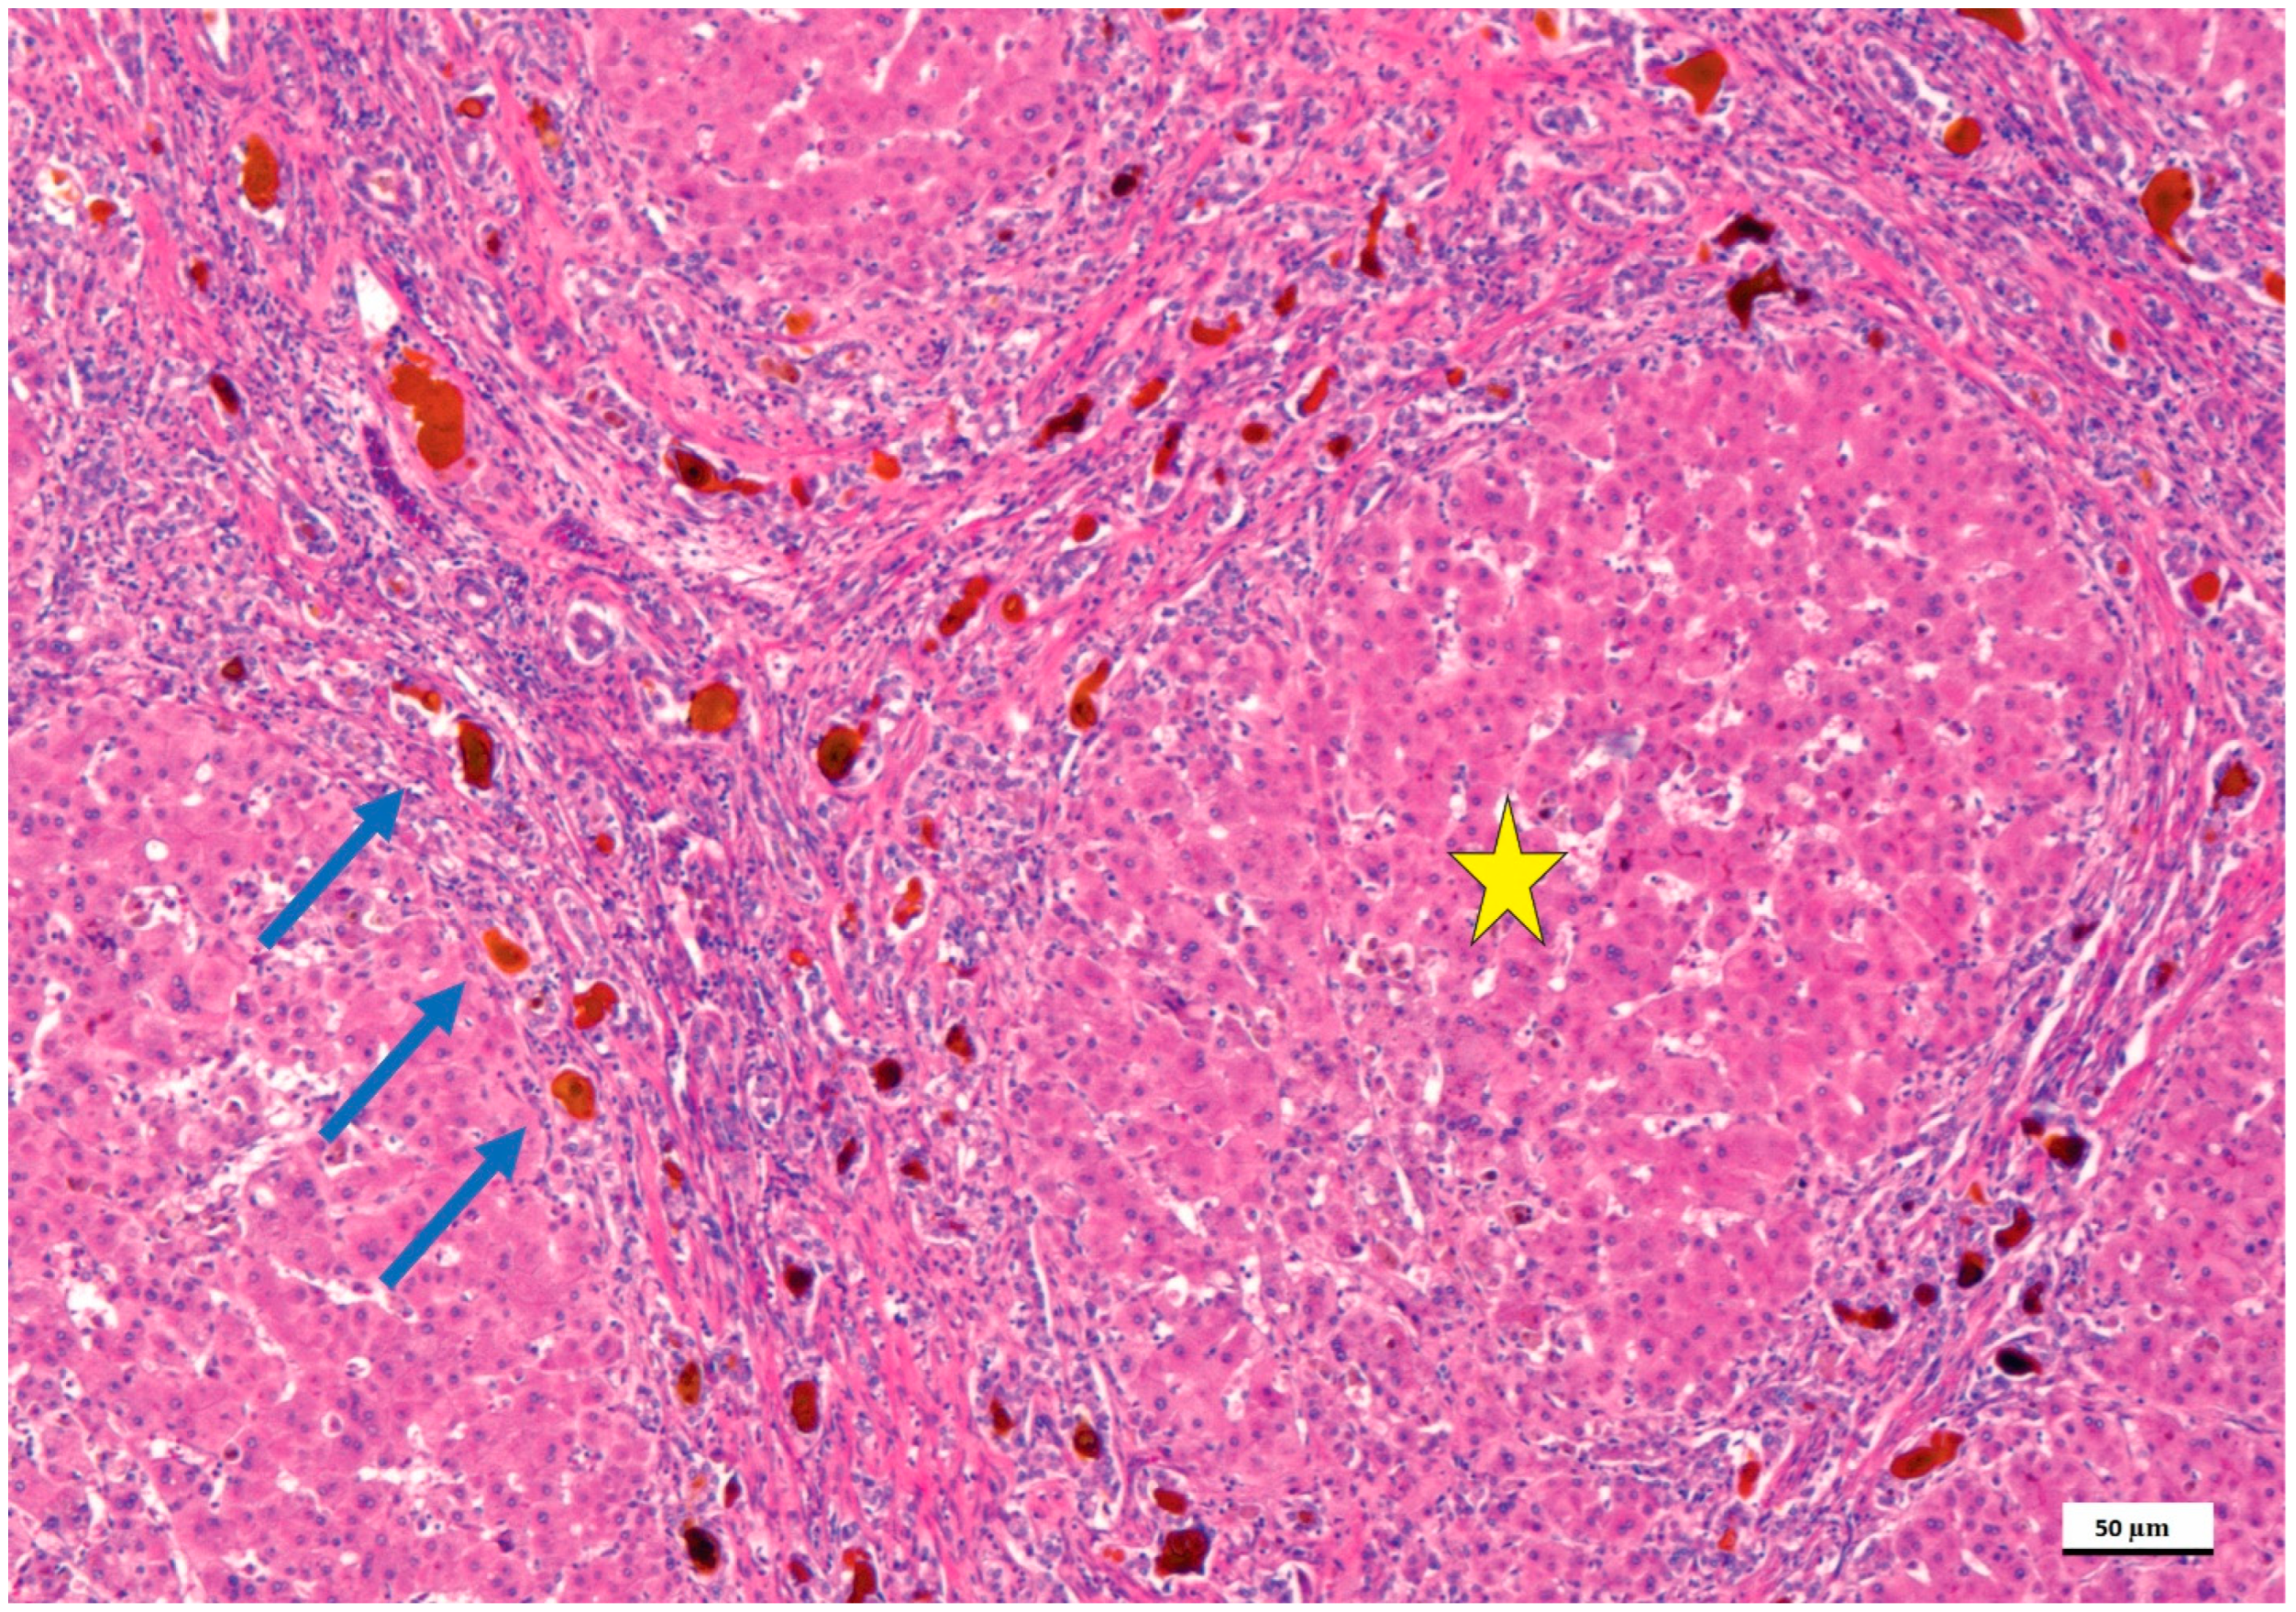

4. Pathological Anatomy of the Biliary Atresia